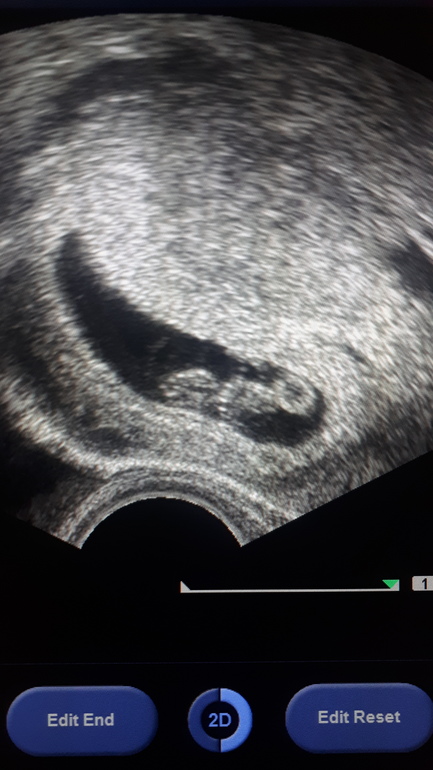

Нам уже 7 неделек😍Полет нормальный

Если было трансвагинально,то девочка Если по животу,то мальчик

Трансвагинальное😁Спасибо,я прочитала про метод,ро не поняла что где🤷‍♀️☺